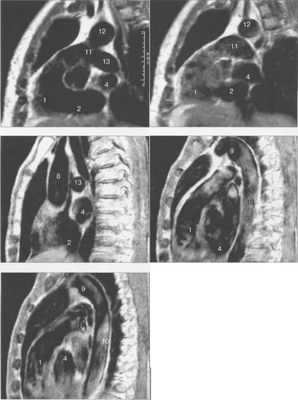

МРТ АНАТОМИЯ СЕРДЦА

МРТ позволяет получать изображения сердца в поперечной (аксиальной), фронтальной (корональной) и сагиттальной плоскостях (ортогональные сечения). Поскольку анатомические оси сердца и магистральных сосудов (за исключением аорты в нисходящем отделе и полых вен) не совпадают со стандартными ортогональными плоскостями исследования, общепринятыми при исследованиях других органов и систем организма, для МРТ-исследования сердечно-сосудистой системы разработаны дополнительные наклонные срезы (двухкамерное сечение, четырехкамерное сечение, сечение по короткой оси левого желудочка).

Рис. 9.48. MPT сердца. Сагиттальная плоскость.

Рис. 9.49. МРТ сердца. Двухкамерные сечения.

Рис. 9.50. МРТ сердца. Фронтальные сечения.

Рис. 9.52. МРТ сердца. Четырехкамерные сечения.

На рис. 9.47—9.52 представлены Т1-ВИ наиболее часто используемых МР-сечений сердца.

Здесь и на рис. 9.48—9.52:

I — правый желудочек, 2 — левый желудочек, 3 — правое предсердие, 4 — левое предсердие, 5 — межжелудочковая перегородка, 6 — межпредсердная перегородка, 7 — задняя стенка левого желудочка, 8 — восходящая часть аорты, 9 — дуга аорты, 10 — нисходящая часть аорты, 11 — легочный ствол, 12 — правая легочная артерия. 13 — левая легочная артерия, 14 — верхняя полая вена, 15 — нижняя полая вена, 16 — трахея.